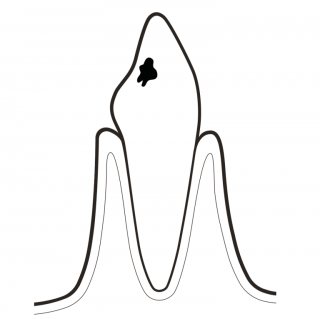

PREVENT CARIES

Biofilm is not always visible to the naked eye. Disclosing biofilm helps to remove all biofilm. GBT prevents caries and gum disease in children and adults. No biofilm = No caries.

DETECT CARIES AT AN EARLY STAGE

Caries often develop in areas not accessible by rubber cups or brushes, such as interdental areas, pits and fissures. AIRFLOW® cleans it all. A final check delivers a more accurate, precise and early detection of caries on clean surfaces. Also, it allows fluoride to access a clean tooth more easily.